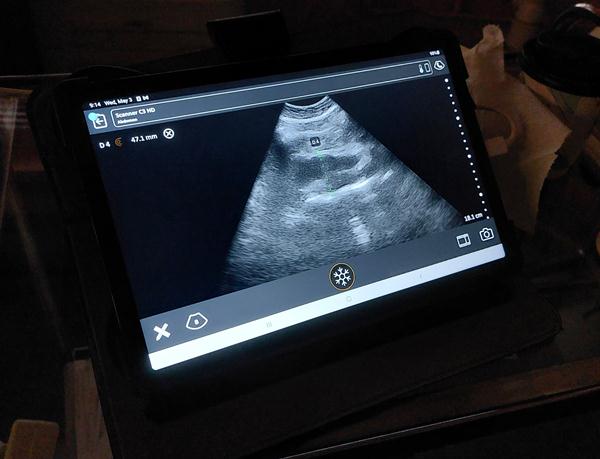

O Δήμος Βέροιας στο πλαίσιο εφαρμογής προγραμμάτων προληπτικής ιατρικής σε συνεργασία με το Ελληνικό Διαδημοτικό Δίκτυο Υγιών Πόλεων του ΠΟΥ (ΕΔΔΥΠΠΥ), μέσα από την Δομή των ΚΕΠ Υγείας του διοργάνωσε από τις 3/5/2023 έως και τις 4/5/2023δωρεάν υπερηχογράφημα με σκοπό την πρόληψη και την έγκαιρη διάγνωση του Ανευρύσματος Κοιλιακής Αορτής.

Οι εξετάσεις πραγματοποιήθηκαν στο Δήμο Βέροιας σε συνεργασία με τους ακτινολόγους ιατρούς κ.κ. ΒασιλικήΚαραδήμου καιΚων/νοΚοτρίδη. Εξετάστηκαν συνολικά (37) πολίτες και σύμφωνα με τα αποτελέσματα (3) από αυτούς είχαν ύποπτα ευρήματα.